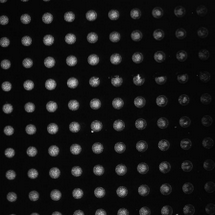

4、药物筛选:用于高通量筛选实验,评估药物对细胞的影响。